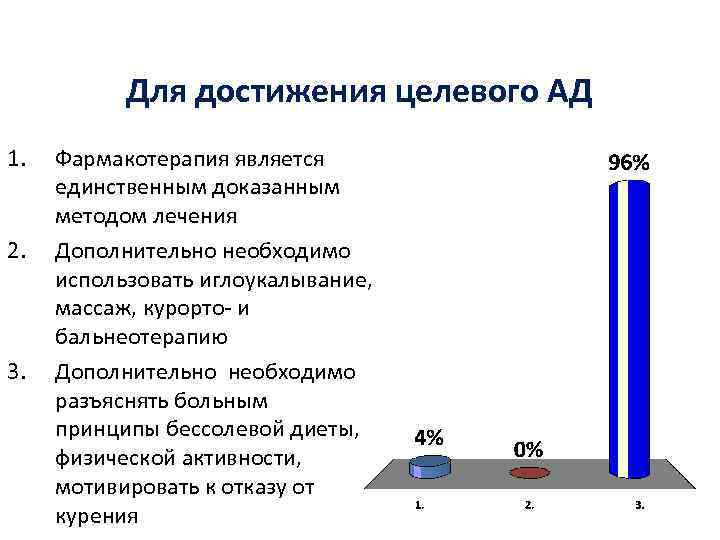

Для достижения целевого АД 1. 2. 3. Фармакотерапия является единственным доказанным методом лечения Дополнительно необходимо использовать иглоукалывание, массаж, курорто- и бальнеотерапию Дополнительно необходимо разъяснять больным принципы бессолевой диеты, физической активности, мотивировать к отказу от курения

Для достижения целевого АД 1. 2. 3. Фармакотерапия является единственным доказанным методом лечения Дополнительно необходимо использовать иглоукалывание, массаж, курорто- и бальнеотерапию Дополнительно необходимо разъяснять больным принципы бессолевой диеты, физической активности, мотивировать к отказу от курения